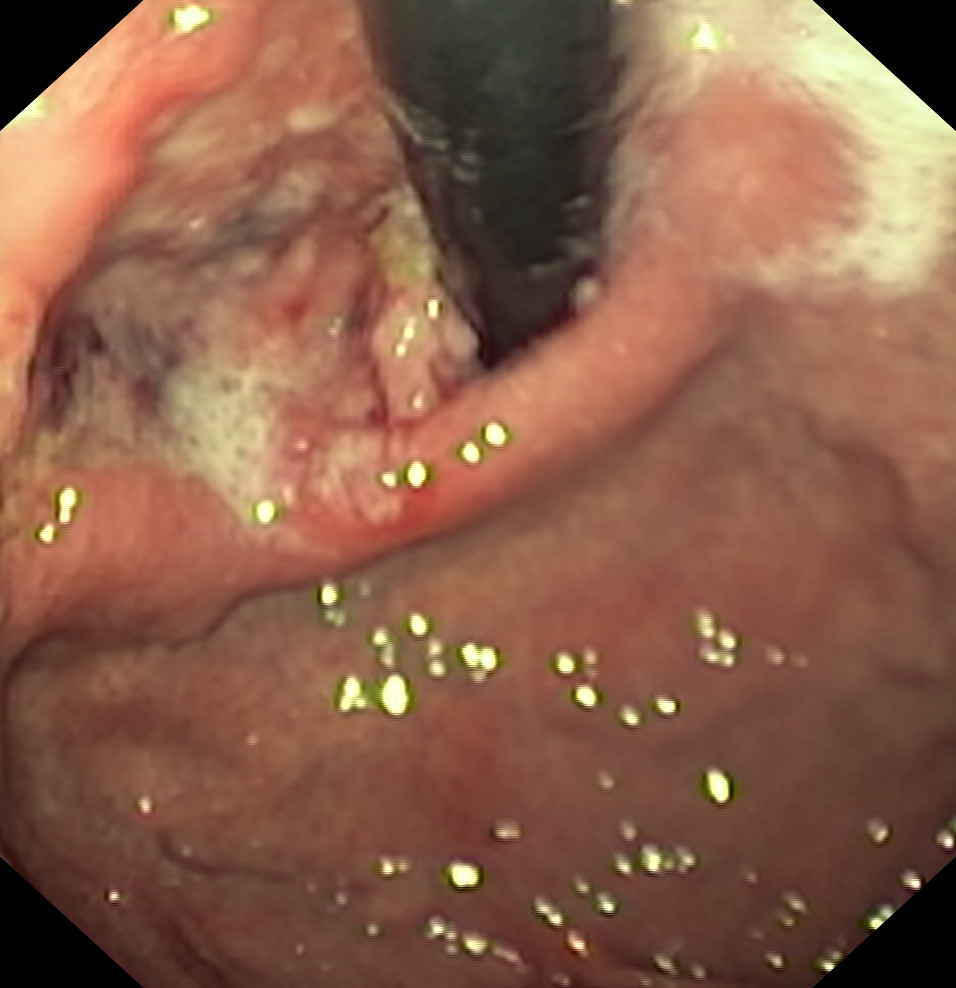

Nowotwory przewodu pokarmowego